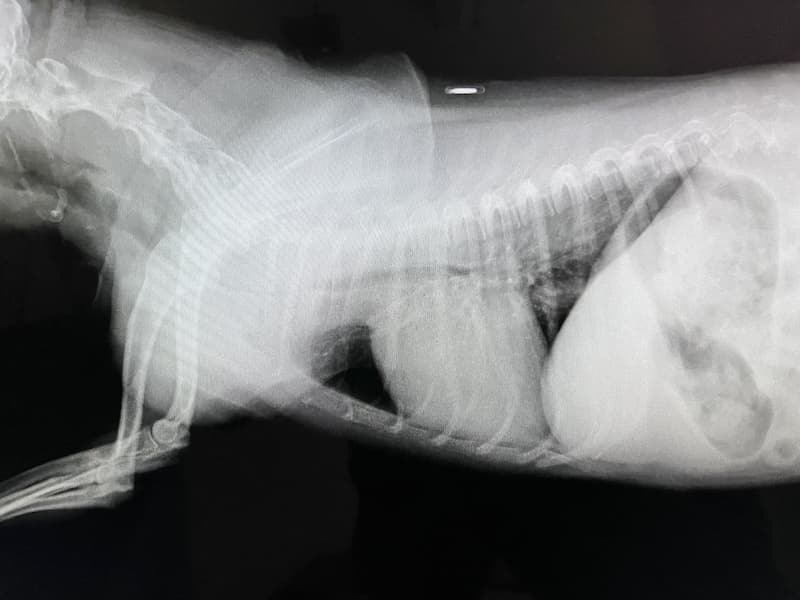

肺水腫(2025/09/01)

肺水腫は、肺に過剰な液体が貯留し、ガス交換が障害され、呼吸が苦しくなる病態です。犬猫では心原性と非心原性に大別されます。心原性肺水腫は、僧帽弁閉鎖不全症や肥大型心筋症などによる左心不全が原因で、左心房の圧が上がり、肺静脈の圧が上昇することで肺に液体が漏出して起こります。非心原性は、外傷、肺炎、敗血症、神経原性などにより血管透過性が亢進して起こります。症状は、浅くて早い呼吸、ゴロゴロとした呼吸音、咳、チアノーゼなどで、急速に悪化することがあります。胸部のレントゲンを撮影し診断を行ないます。治療は心原性では酸素吸入、利尿薬、血管拡張薬や強心薬などで行ないます。非心原性では酸素投与と原因に応じた治療を行ないます。迅速な対応が必要となる病態のため呼吸様式の異常を感じた場合は早めにご相談ください。

獣医師 神野